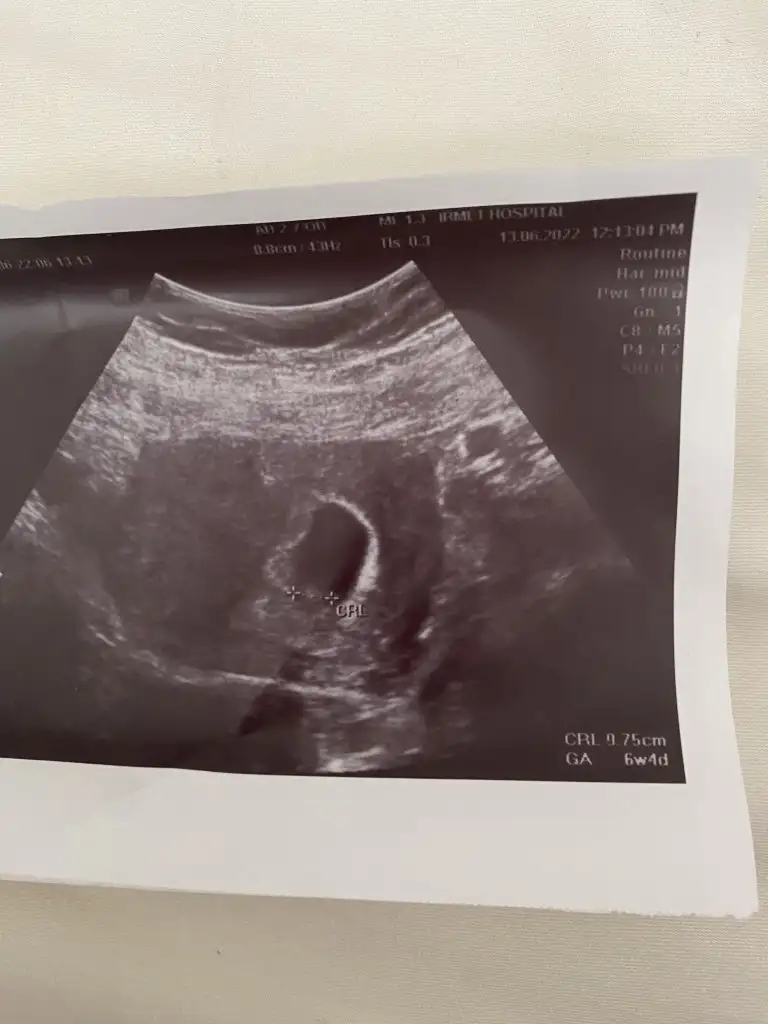

Merhaba başka bir görsel buldum bu daha net 6 hafta 4 günlük karındançok ortada, başka görüntü var mı?

paşa gibi emin değilimMerhaba başka bir görsel buldum bu daha net 6 hafta 4 günlük karından

Evet son olarak kız sanırım karardediğiniz gibi prenses gibi yerleşmiş

Diye tahminde bulunmuştunuz ama cinsiyetinin erkek olduğunu söyledi doktorum.prenses gibi kuzum